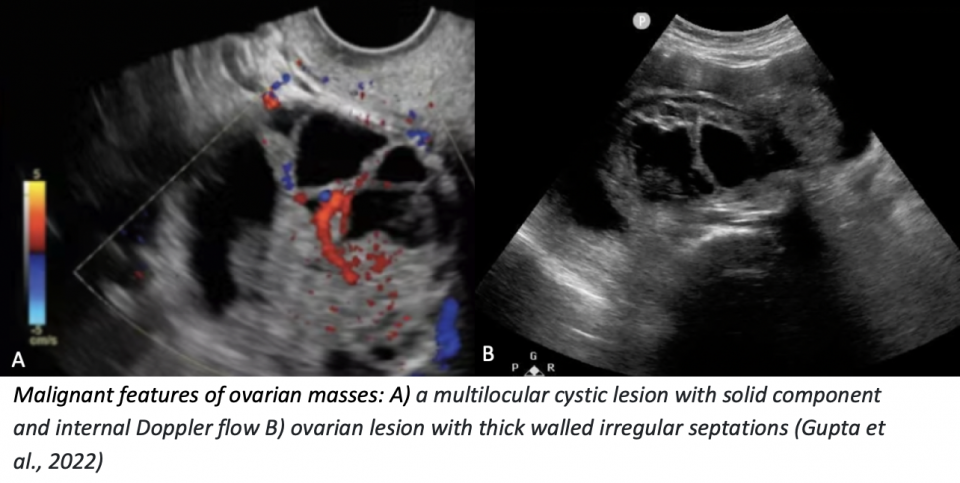

Neoplastic / Malignant Features

PoCUS features

- Thick-walled (> 2–3 mm), irregular septations

- Solid components with vascularity on Doppler

- Papillary projections (especially with flow)

- Ascites or peritoneal implants may be seen

Management / Follow-up

Radiology-performed ultrasound ± CT

Gynecology referral